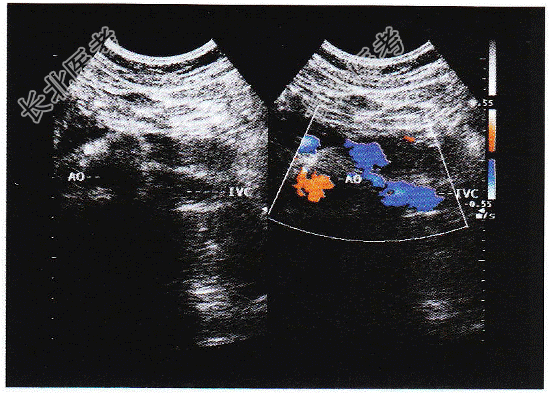

- 单项选择题临床资料:女, 34岁,右位心。

超声综合描述: 右上腹可见脾脏(图1),左上腹可见肝脏(图2), 腹主动脉位于脊柱右前方,下腔静脉位于脊柱左前方(彩图), 胆囊位于左上腹(图3),各脏器形态大小回声未见异常。